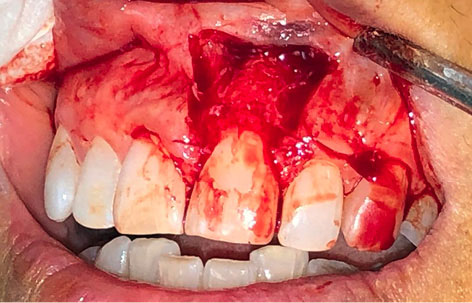

A 52-year-old female patient referred to the Department of Periodontics at Tabriz University of Medical Sciences, complaining of esthetic problems due to a soft tissue lesion located on the gingiva of left maxillary central incisor, without pain, with a history of almost seven years and several attempts of incomplete removal and recurrence (Figure 1).

japid-12-95-g001

Figure 1. Soft tissue lesion, preoperative photograph

The last biopsy had led to a diagnosis of a peripheral ossifying fibroma. Recurrence had occurred due to incomplete removal of the lesion. Intraoral examination revealed a lesion measuring approximately 1×0.6×0.5 cm, which was nodular, exophytic, and sessile. The radiographic image showed normal structures and no related changes.